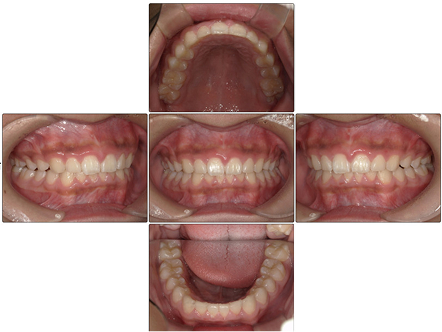

過蓋咬合 【10代・男性】

お口の中全体の写真

Before

After

- 学校の歯科検診で【歯並び悪い】とチェックがあったため矯正相談された方です。診察したところ下の前歯部に叢生を認め、前歯部に過蓋咬合(ディープバイト)で咬合関係の不正も認めました。

- 上下の叢生は改善され、過蓋咬合だった咬合関係も治って綺麗な歯並びとなりました。